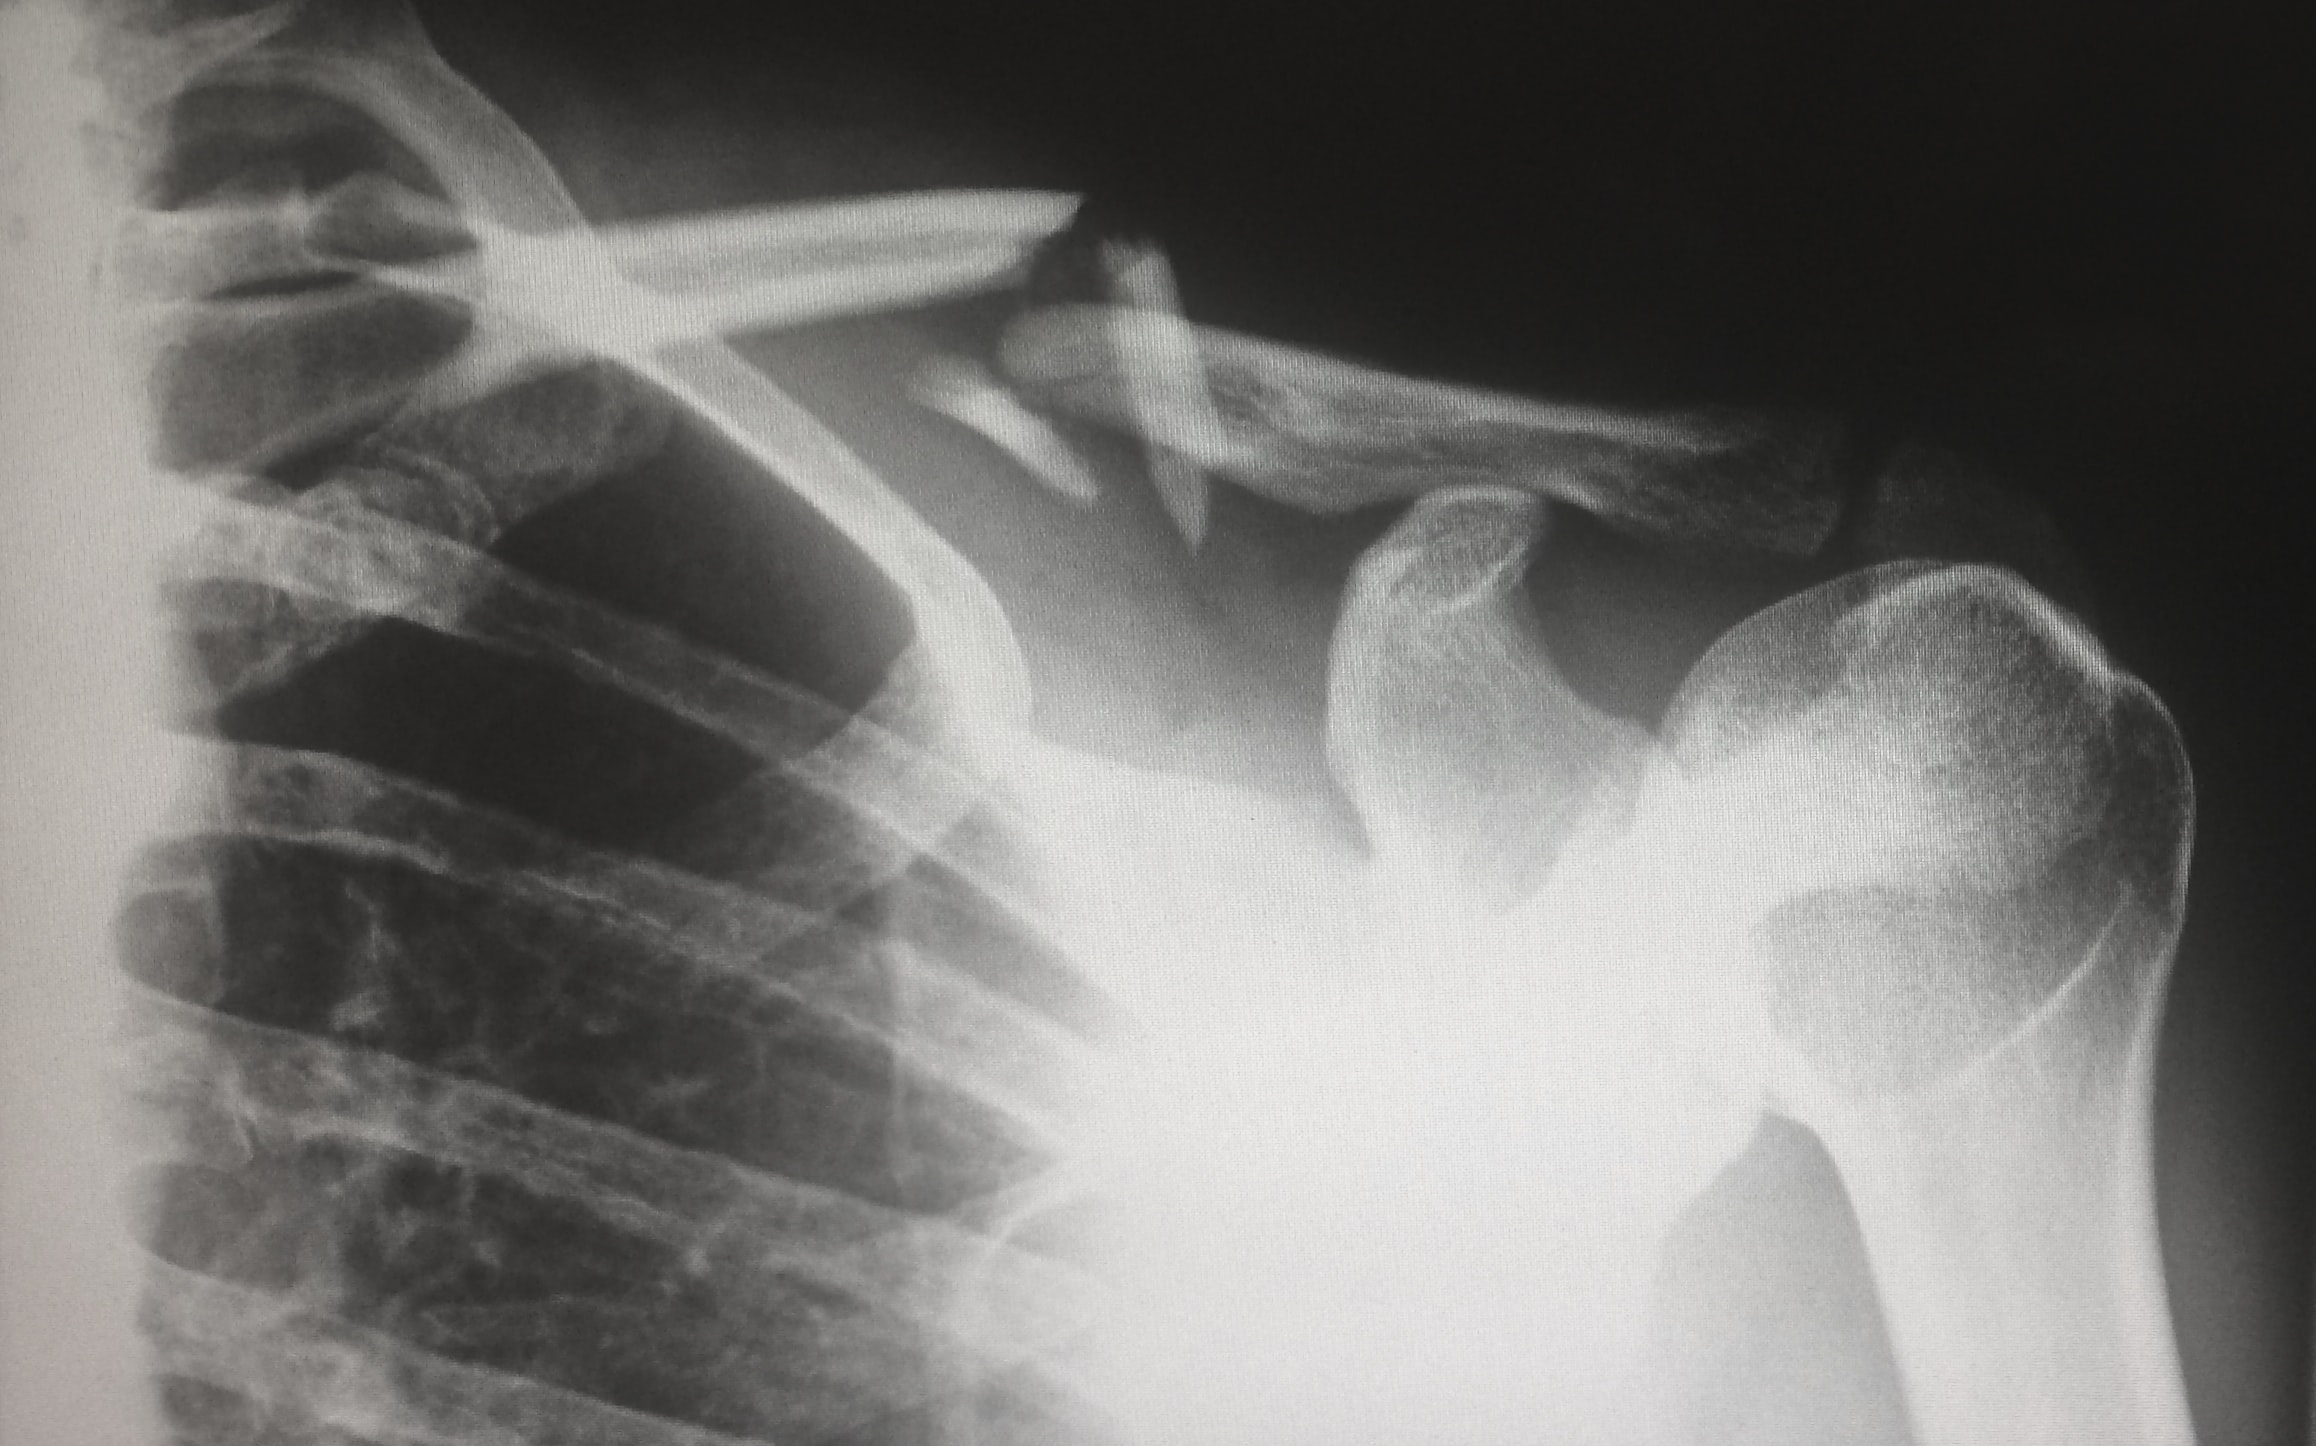

석회성건염

석회성건염이라는 질환은 연세가 조금 있으신 분들에게 잘 나타납니다. 노화로 인한 혈액순환 문제로 어깨 힘줄에 석회가 침착되서 힘줄과 근육을 자극하면서 생기게 되는 질환입니다.

이는 어깨를 여러 방향으로 움직이고자 할 때 심각한 통증을 발생시키는데요. 특히 자려고 누웠을 때 어깨통증을 느낀다면 석회성건염일 가능성이 많습니다. 누웠을 때 우리 체중이 어깨로 쏠리면서 석회가 힘줄을 자극하게 되어 어깨통증 원인이 됩니다.

위와 같은 증상이 나타나면 엑스레이 검사를 통해 자세히 진단해보고 문제가 있다면 바로 적절한 치료를 시작하시기는 것이 좋습니다. 초기에는 약물치료와 체외충격파 치료를 병행하면서 금방 호전이 되기는 하나 증상이 심해지면 수술이 불가피할 수 있으니 그전에 반드시 치료를 시작하시기를 바랍니다.